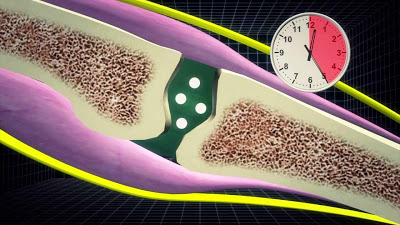

Μια άλλη θεωρία είναι ότι οι φυσαλίδες αζώτου στο υγρό στο εσωτερικό της άρθρωσης διαλύονται ή δημιουργούνται κατά την κίνηση της άρθρωσης. Φαίνεται ότι στις αρθρώσεις, λόγω της συνεχούς κίνησης τους, δημιουργούνται μικρές φυσαλίδες που περιέχουν διάφορα αέρια, που ευρίσκονται φυσιολογικά διαλυμένα στο αρθρικό υγρό, όπως το διοξείδιο του άνθρακα, οξυγόνο και άζωτο. Οι φυσαλίδες αυτές όταν συμπιεστούν κατάλληλα, κινούνται με τόση πίεση, διαρρηγνύονται και παράγουν τον χαρακτηριστικό ήχο.